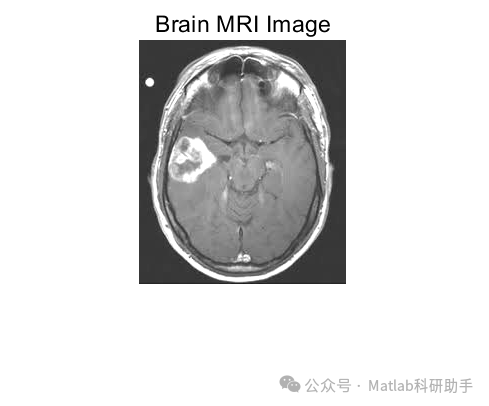

脑磁共振(MRI)图像分类是医学影像分析的重要任务,在阿尔茨海默病诊断、脑肿瘤分级等领域具有关键应用。基于主成分分析(PCA)和核支持向量机(Kernel SVM)的分类器,通过 PCA 实现特征降维与去噪,结合核 SVM 的非线性分类能力,能有效处理 MRI 图像的高维度、强噪声特性,实现精准分类。